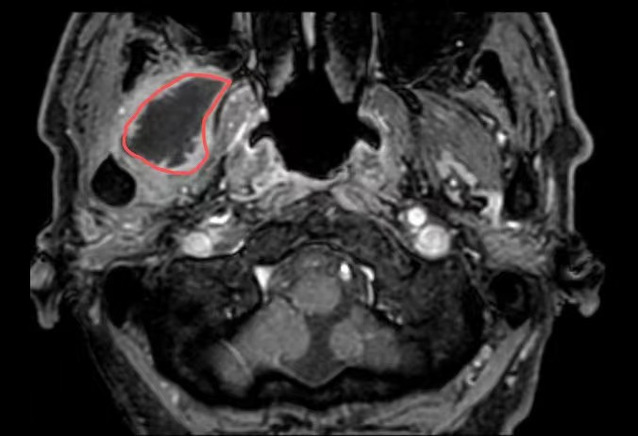

在苏州九院超声介入科,徐斌主任就接诊了这样一位患者。一个月前,患者熊先生脸颊部隐隐作痛,到医院一查是牙齿发炎了,抗炎后熊先生拔除了发炎的牙齿。但是,回家后没几天,面颊部就又开始疼痛、发热。经过反复就医、检查、消炎止痛后做增强磁共振提示:右翼外肌及颞肌异常信号,考虑脓肿可能,相关科室的医生和熊先生说这个手术可能比较复杂,需要行开放性手术。

△磁共振提示病灶(红圈处)